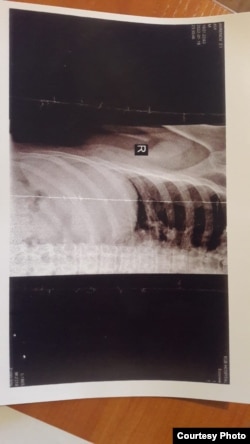

— Моего брата завели в кабинет, позвали специальных сотрудников СОБРа и сказали: «Из России приехали сотрудники ОМОНа, сейчас они тебя хорошенько побьют». Через пару минут заходят три сотрудника в масках, заместитель начальника полиции указал на моего брата и сказал: «Отработайте». И его в это время начали бить со всех сторон, — рассказывает Амренов. — Ему сломали ребро, около 15 минут избивали. Один сотрудник сказал: «Если их не будешь слушаться, избиение продолжится».

— Там же у него был суд, дали 10 суток ареста. Моего брата избили, пытали и закрыли на 10 суток. На освидетельствование телесных повреждений Зарлыка не возили. Он просил вызвать врача, но ему отказали, сказав, что задержанный притворяется. Закрыли на 10 суток со сломанным ребром и сломанным зубным протезом. Когда он вышел, мы всё зафиксировали, — рассказывает Калиаскар.